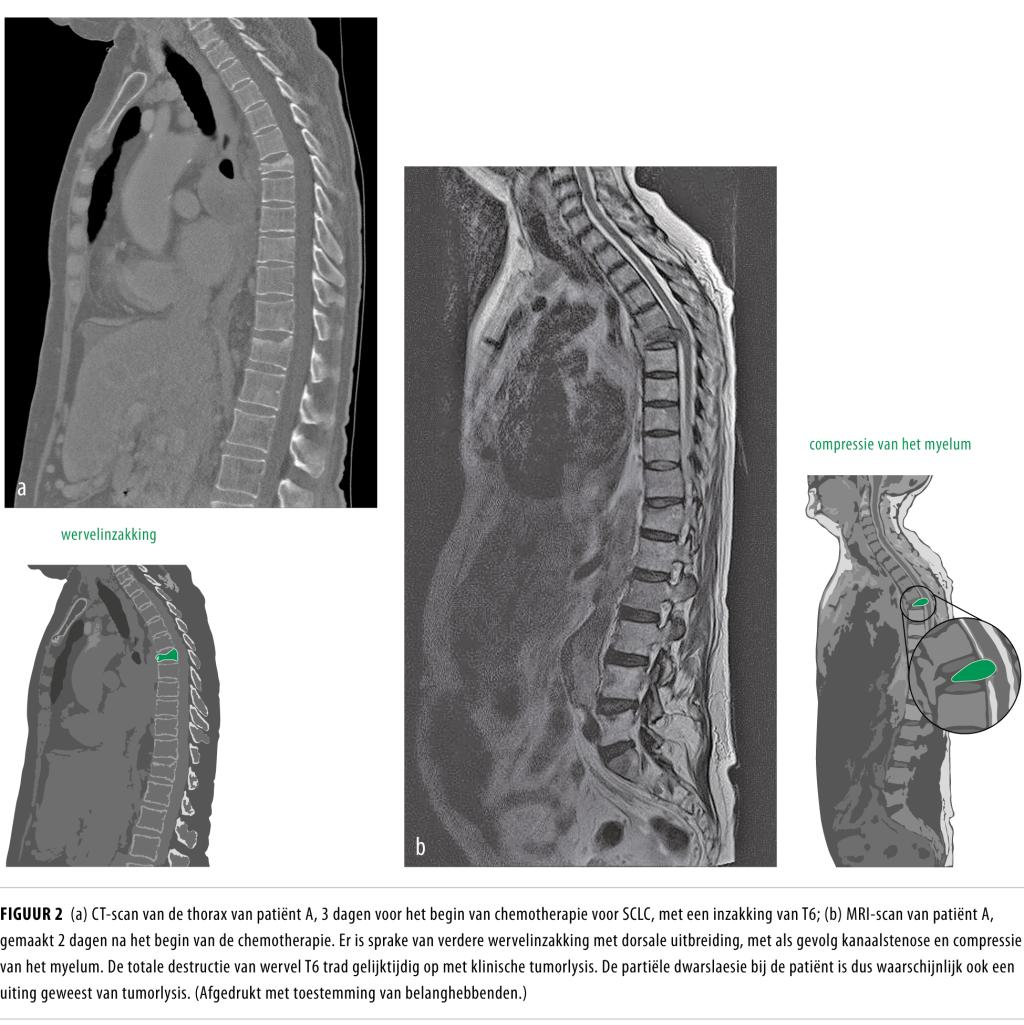

Tumorlysissyndroom bij kleincellig longcarcinoom NTvG